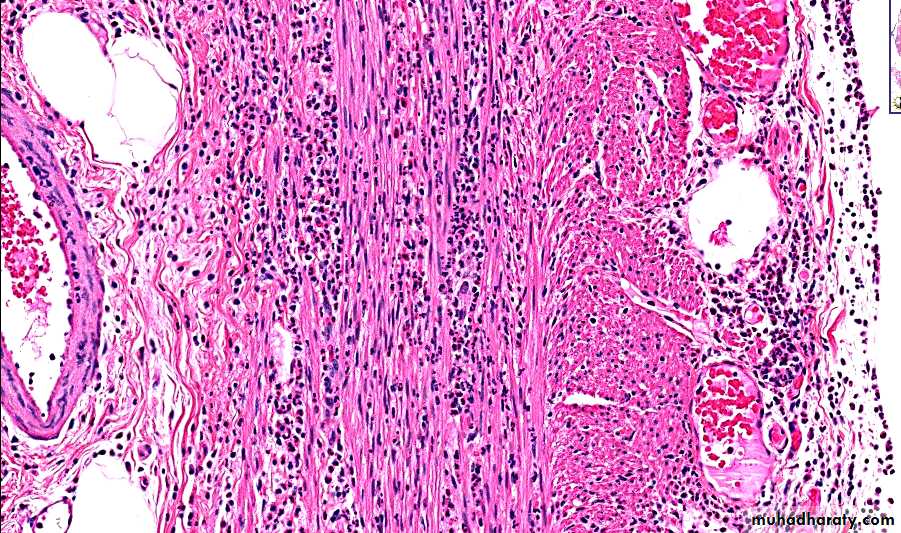

The base show fibrinoid material, Beneath this, active granulation tissue infiltrated with mononuclear leukocytes and a fibrous or collagenous scar

Morphologically: formation ofpseudomembranes made up of an adherent layer of inflammatory cells and debris at sites of colonic mucosal injury.

The surface epithelium is denuded, and the superficial lamina propria contains a dense infiltrate of neutrophils and occasional fibrin thrombi within capillaries.

These exudates coalesce to form the pseudomembranes